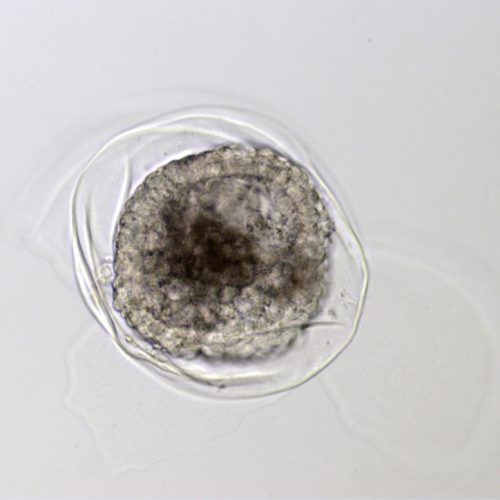

- Capsule: The embryonic capsule is unique among domestic mammals. This is a glycoprotein protective coat formed by the trophoblast layer beneath the zona pellucida. It forms only after the embryo enters the uterus, so embryos grown in a laboratory do not develop the capsule until after they are transferred. If not protected by either the zona pellucida or the embryo capsule, an embryo cannot survive in the uterus.

- Growth rate: Once the embryo becomes a blastocyst and starts expanding around day seven, the embryo will nearly double in size each day until day 12. This allows early ultrasound determination of pregnancy status, as an embryo around 300-400 microns (0.3-0.4mm) in size when recovered at day seven will grow to 3-4mm, large enough to be visualized on an ultrasound scan, by day 11.